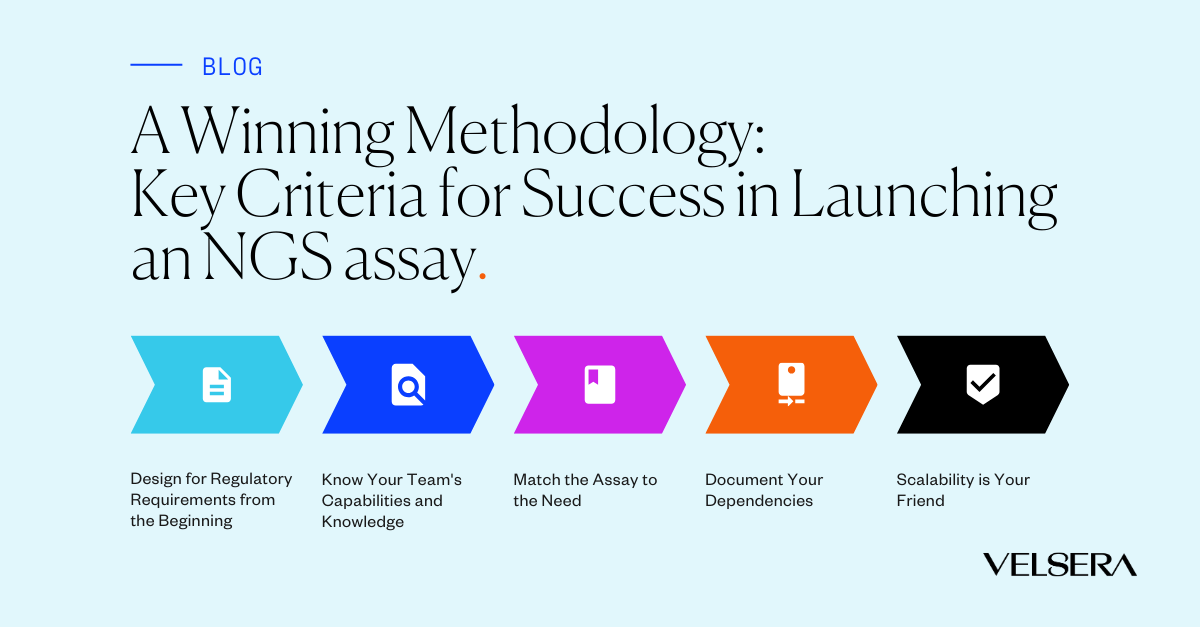

Blog

On October 29, 2024 | By Christopher Wilkinson